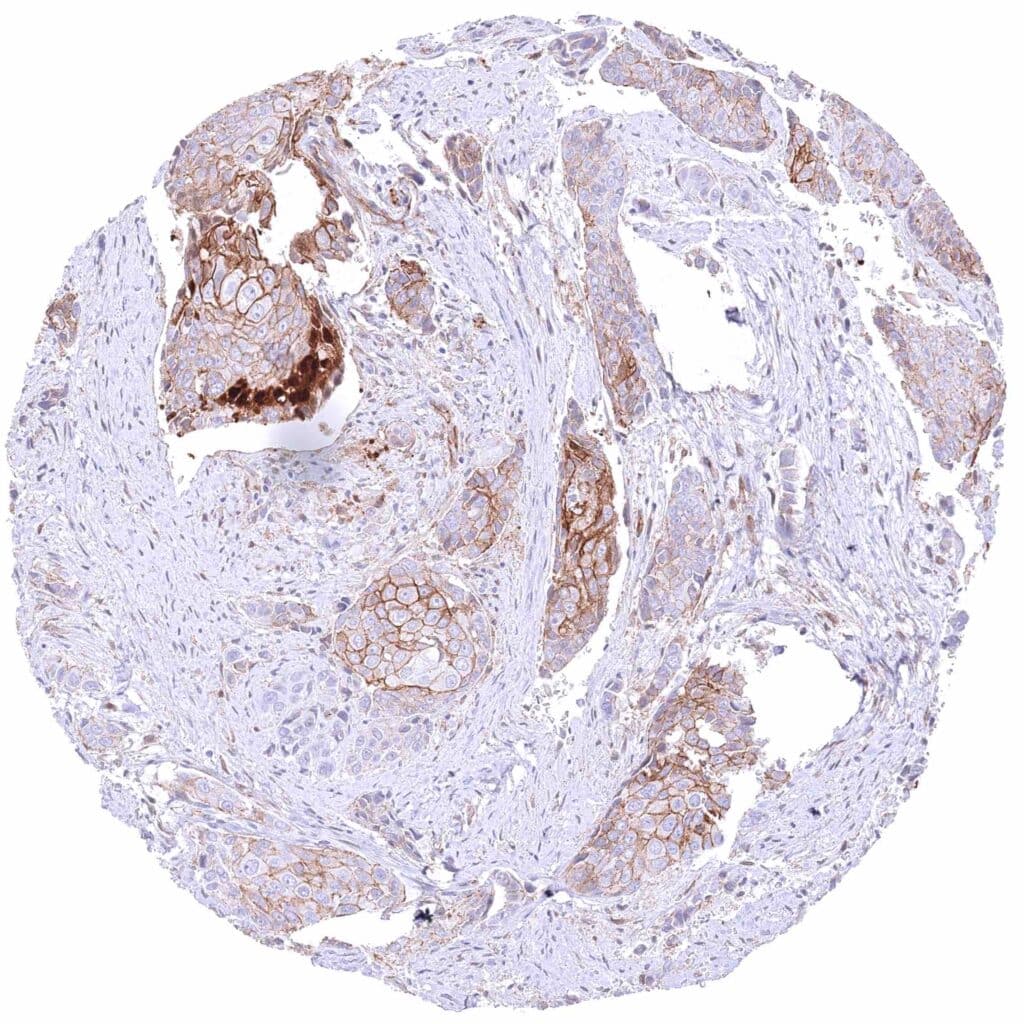

Pancreas – Ductal adenocarcinoma with strong membranous β-Catenin staining of tumor cells possibly accompanied by a mild cytoplasmic positivity.